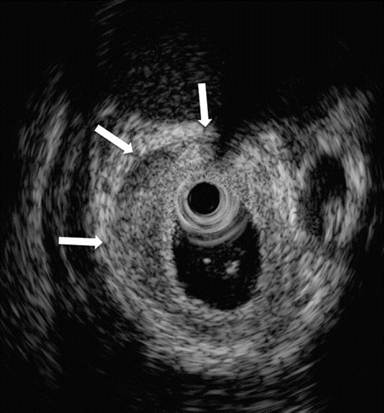

A 24-year-old man presenting with jaundice and elevated levels of IgG4 (366 mg/dL; reference range: 8-140 mg/dL). Magnetic resonance cholangiopancreatography (MRCP) was requested; the T2-weighted coronal scan (Image 1a) showed dilated intra- and extra-hepatic bile ducts with an abrupt stricture (arrow) of the intrapancreatic common bile duct; the pancreatic duct was narrowed throughout its course. Subsequent EUS (Image 1bc) revealed a diffusely and substantially enlarged pancreatic gland (arrowheads) with echopoor echotexture and a normal main pancreatic duct having a diameter of 1.3 mm (Image 1b, arrow), measured with calipers (Image 1c, arrow). Hyperechoic septa were well visible in the enlarged gland. Stenosis of the distal bile duct was due to a diffuse thickening of the wall with an intermediate echopoor layer, and echorich outer and inner layers ("sandwich-pattern") (Image 1d, arrowheads).

Image 1 |